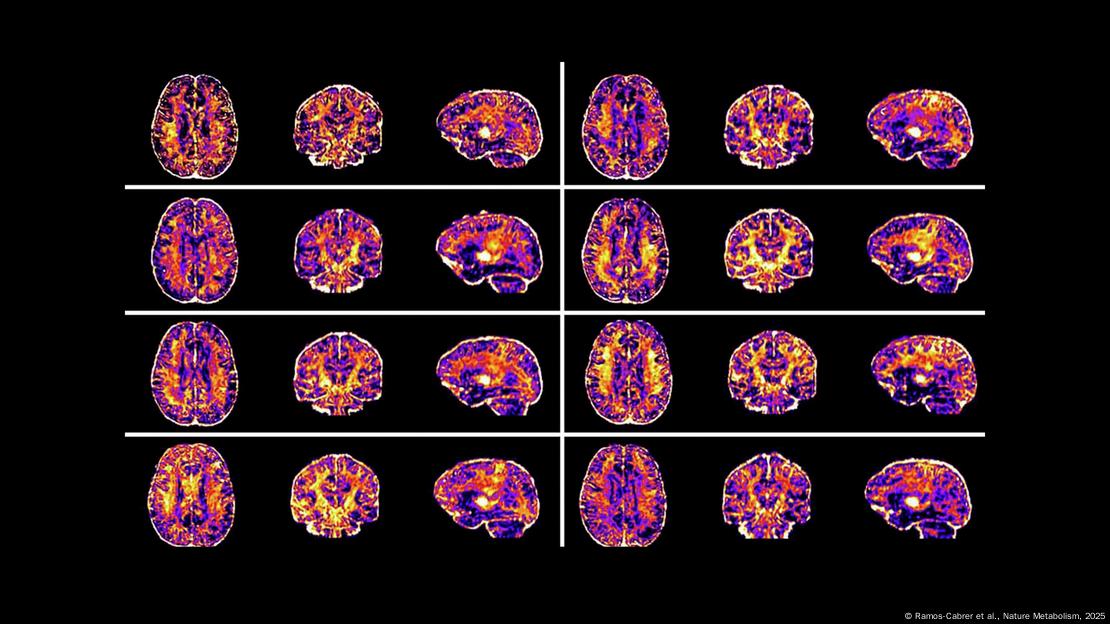

Analizaron las resonancias magnéticas para estudiar el área superficial y el grosor de las regiones en la corteza, incluidas las involucradas en funciones cognitivas superiores como la memoria, la atención, la emoción y el lenguaje.

También examinaron las conexiones entre diferentes regiones del cerebro utilizando resonancias magnéticas, donde los cambios en el flujo sanguíneo indican la actividad cerebral.

*Resonancias de más niños estadounidenses confirman que las brechas sociales afectan al neurodesarrollo y elevan el riesgo de depresión y ansiedad en la niñez y la adolescencia | Nature Mental Health

Los escáneres mostraron que los niños que viven en áreas con mayores niveles de desigualdad social están asociados con una superficie reducida de la corteza y conexiones alteradas entre múltiples regiones del cerebro.

Estos hallazgos proporcionan evidencia de un neurodesarrollo afectado, que podría relacionarse con la salud mental y la función cognitiva futuras, defienden los autores.